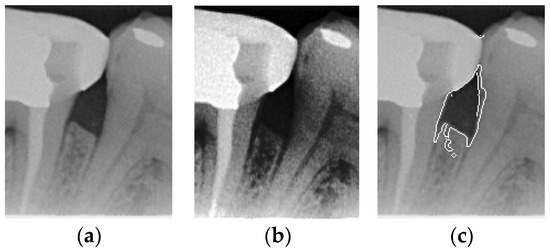

2.3.1. Bilateral Filter

The original image has a lot of noise, which needs to be eliminated to smoothen the image. This study initially adopts median filtering, which is a non-linear digital filtering technique that is commonly used to remove noise. However, this method is not effective. In order to filter out the noise and preserve the edge details of the image at the same time, this study uses bilateral filtering (1) to solve this problem, which is shown in Figure 3.

Figure 3. Comparison of filtering effects. (a) Original image. (b) Median filter. (c) Bilateral filter.